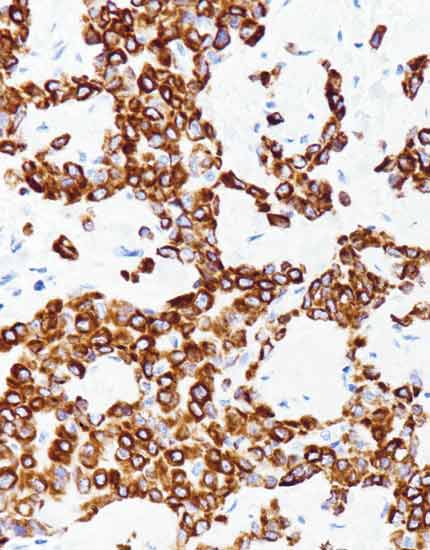

产品名称:c-Met

产品编号:RMA-1039

阳性部位:胞膜/胞质

图片描述:

肺腺癌,c-Met染色,细胞膜/细胞质阳性